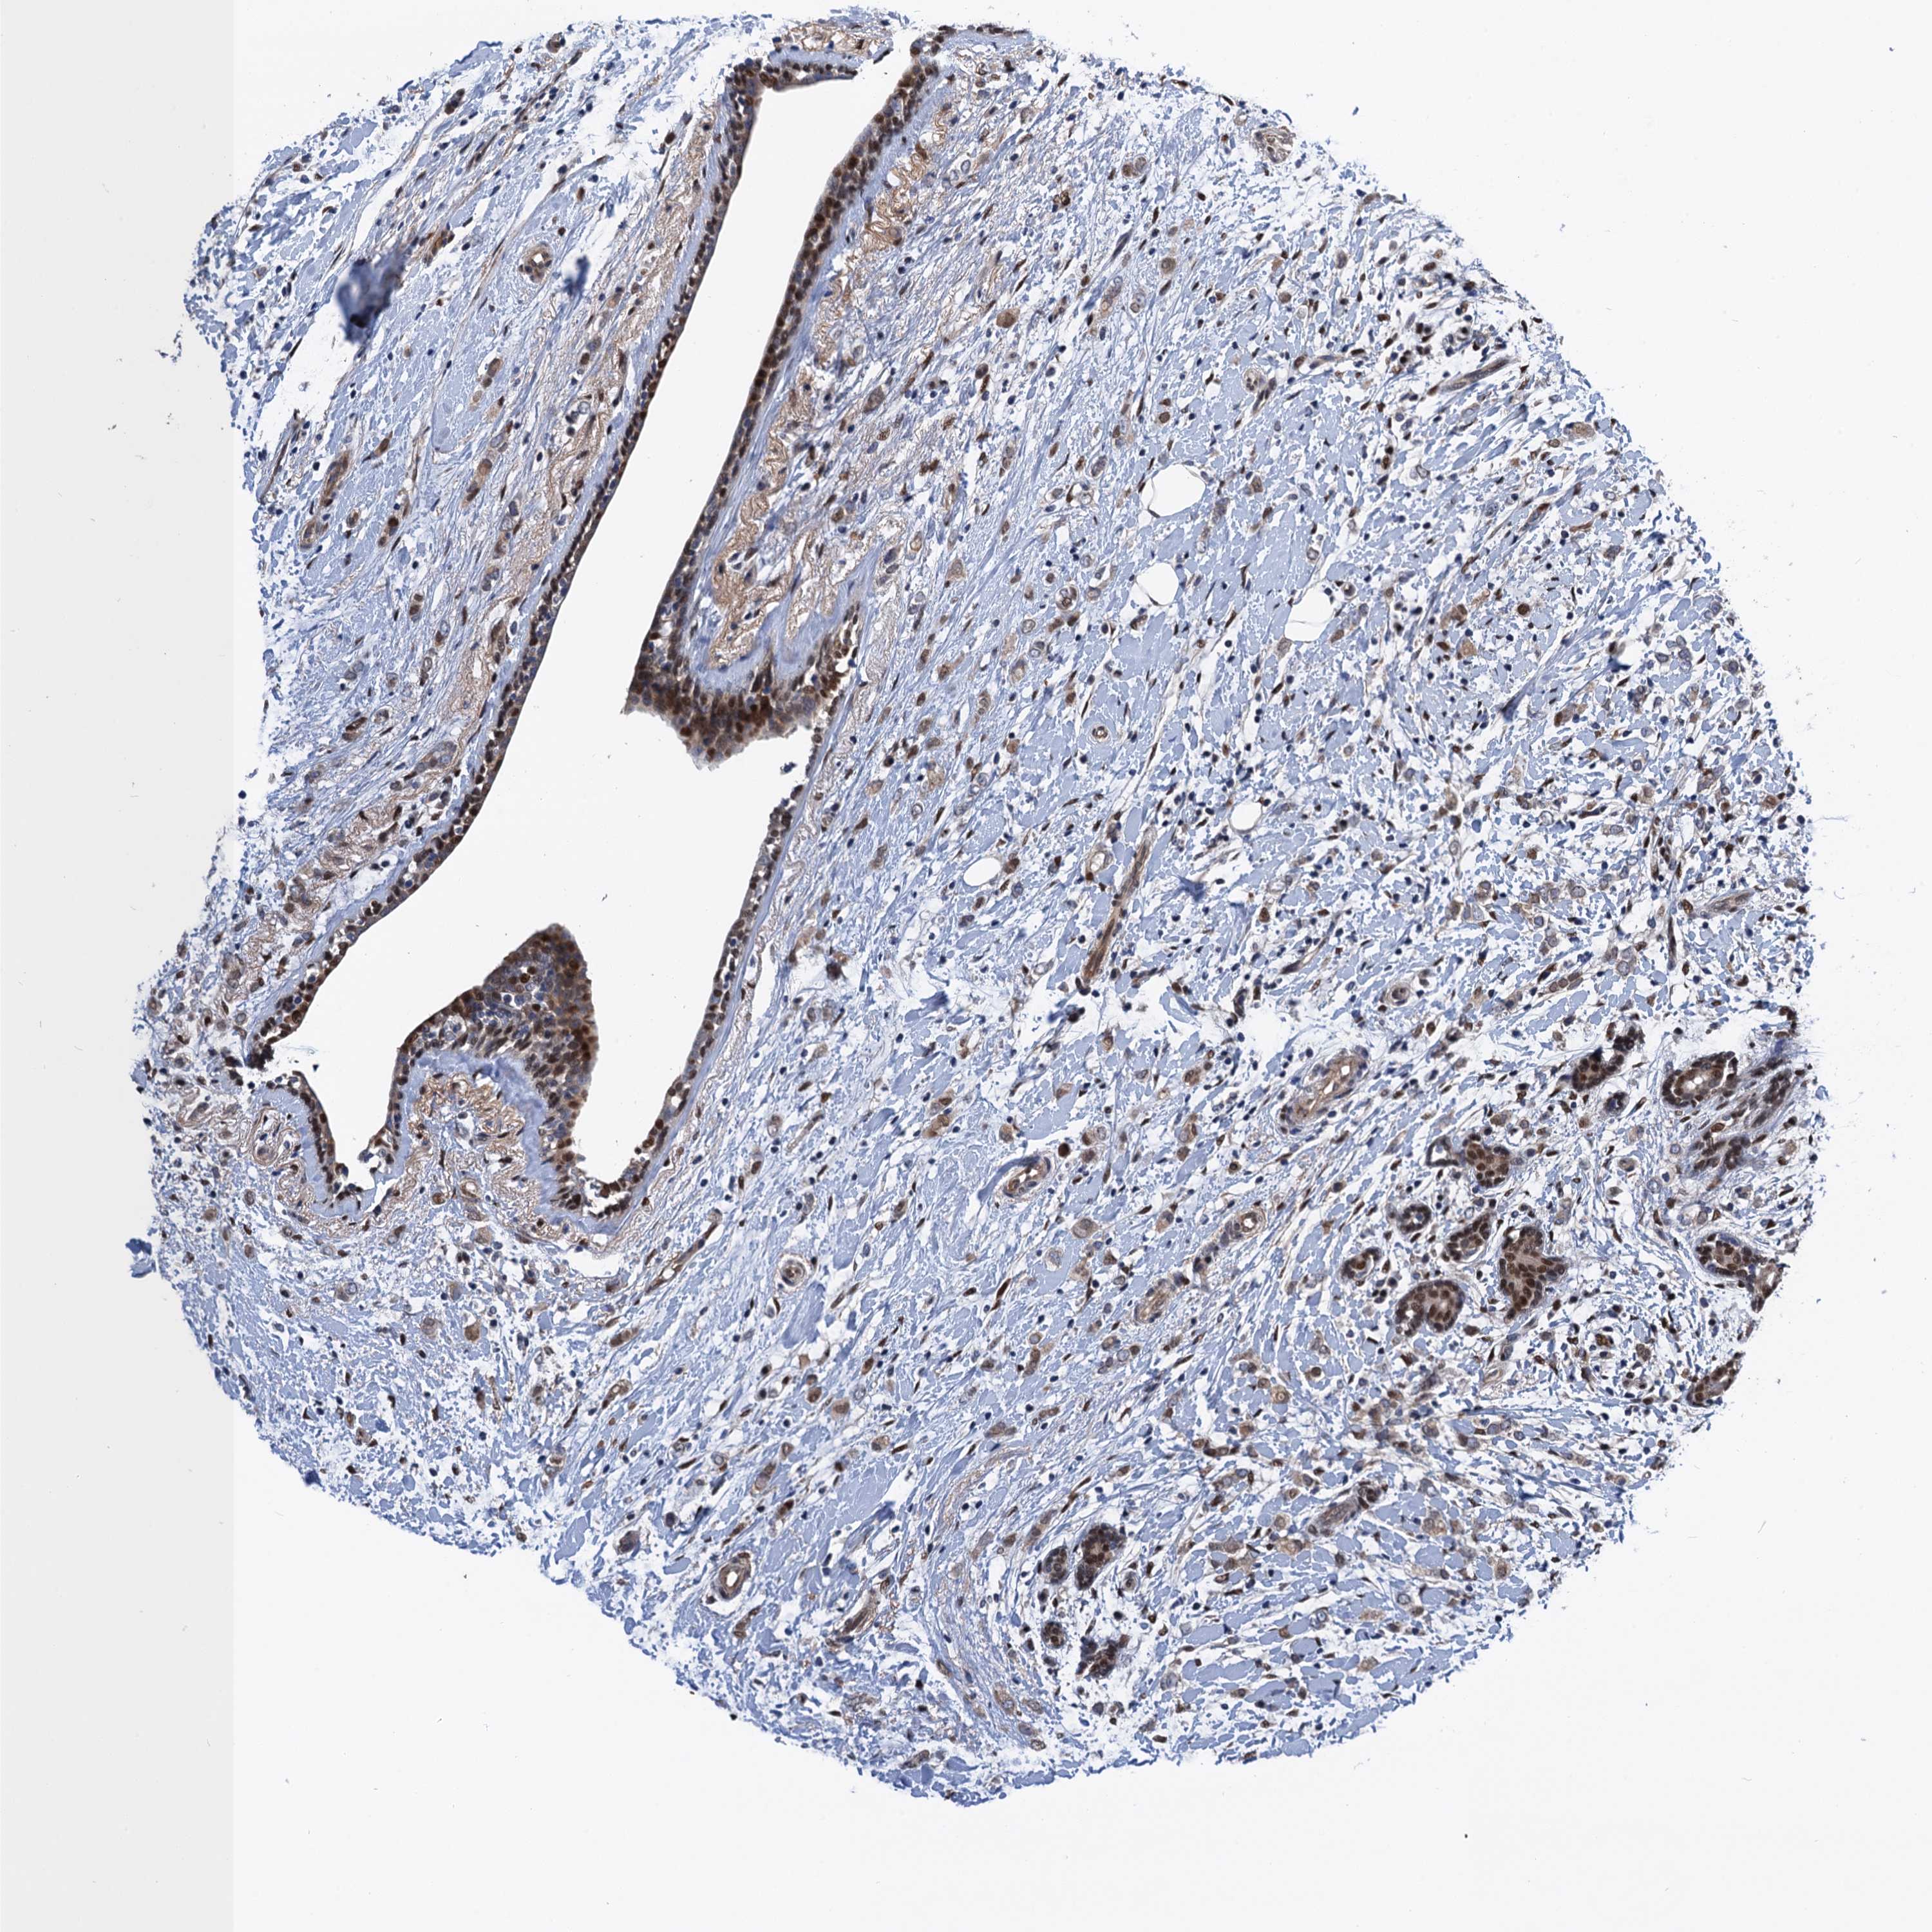

CANCER BREAST CANCER Show tissue menu

BRCA TCGA BRCA VALIDATION PROTEIN EXPRESSION

Breast cancer

Human cancer

GDPD3 is not prognostic in Breast Invasive Carcinoma (TCGA)